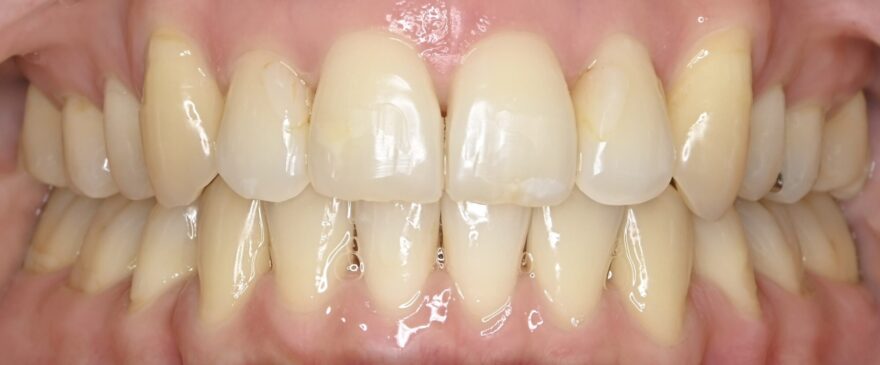

治療後の口腔内写真

約2年の動的期間(歯を動かす時期)で、ここまで美しい歯並びになりました。

ベーシックな表側矯正を選んで頂いても、最終的な仕上がりに差はありません。

前歯のガタガタが無くなりました。

前歯には後戻りを防止するための保定装置が装着されています。